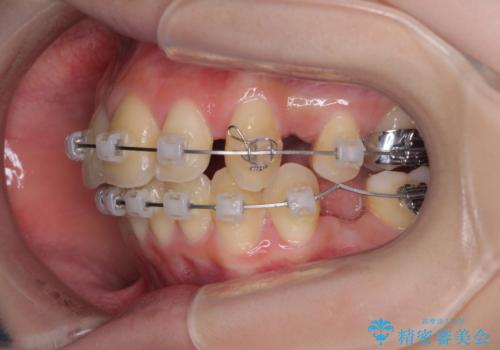

出っ歯を治したい ワイヤー装置による抜歯矯正

- クリアブラケット

- 上下の出っ歯を気にして来院された患者様です。

口元を積極的に引っ込めるために、上下左右の小臼歯を4本抜歯することとしました。

右上前から2番目の歯が欠損しているため、①矯正治療により欠損部にスペースを作りインプラント補綴を行って前歯を左右対称に揃える、②左右非対称となるが、欠損補綴を行わずに排列する、のいずれかとなりますが、患者様と相談の上②にて矯正治療を行うこととしました。

変則的な歯列であったため、奥歯がしっかりと咬み合うのか、前歯はしっかりと排列できるのかと不安ではありましたが、結果としてはきれいに整った歯列にて終了することができました。